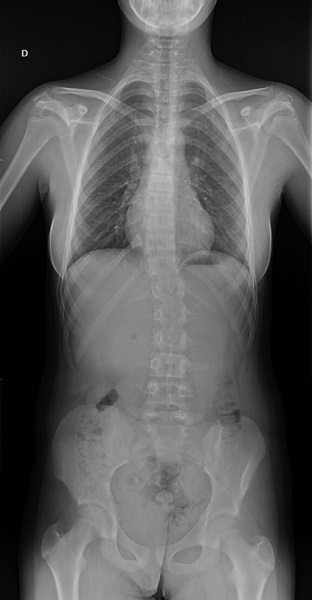

Tras la intervención, presentó escoliosis secundaria, dorsal derecha y lumbar izquierda, mínimo ascenso de hombro y pelvis derecha e hiperlordosis (Figura 3). Debido al sobrecrecimiento, la extremidad inferior izquierda era más corta y se equilibró con alza de 8 mm.

| Figura 3. Radiografía en la que se aprecia escoliosis secundaria tras la segunda intervención quirúrgica |